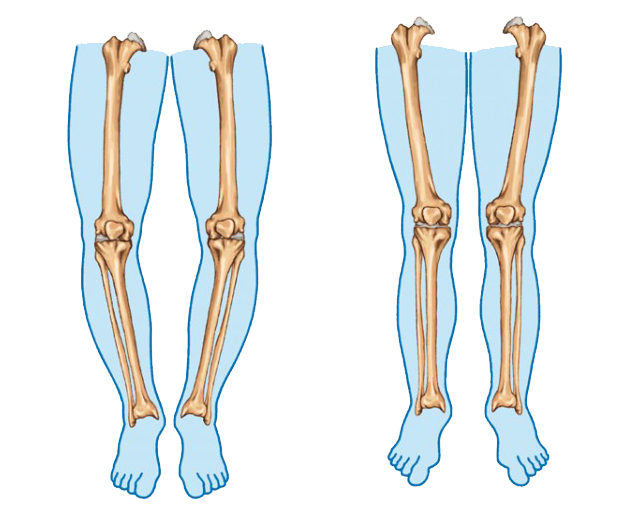

Bow legs, also known as genu varum, is a condition where the legs appear bowed outwards when standing. This condition can cause discomfort, pain, and even difficulty walking. In severe cases, surgery may be required to correct the alignment of the legs. In this article, we will discuss the causes, symptoms, and treatment options for bow legs, including the various surgical procedures available.

Knock Knees, also known as genu varum, is a condition where the legs appear bowed outwards when standing. This condition can cause discomfort, pain, and even difficulty walking. In severe cases, surgery may be required to correct the alignment of the legs. In this article, we will discuss the causes, symptoms, and treatment options for Knock Knees, including the various surgical procedures available.